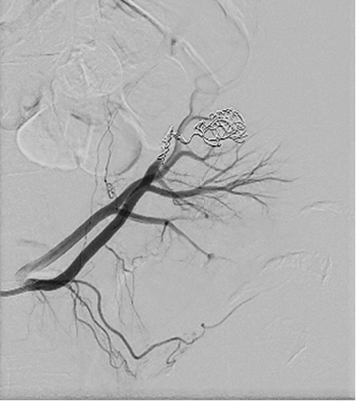

A 52 year old woman arrived at a hospital for a routine health check-up. Abdominal ultrasound revealed a 4.5 cm diameter lesion in the right kidney. Patient was directed to perform a contrast-enhanced computed tomography (CT), which was performed to specify the nature of the formation. CT found 49 mm x 34 mm cyst in the middle-lower portion of right kidney with septum and contrast accumulation (Figure 1), it was classified as Bosniak III and partial nephrectomy was chosen as a main choice of treatment.

Figure 1. A contrast-enhanced Computed Tomography of abdomen was performed (a 49 mm x 34 mm cyst in the middle-lower portion of right kidney with septum and contrast accumulation was found (white arrow)